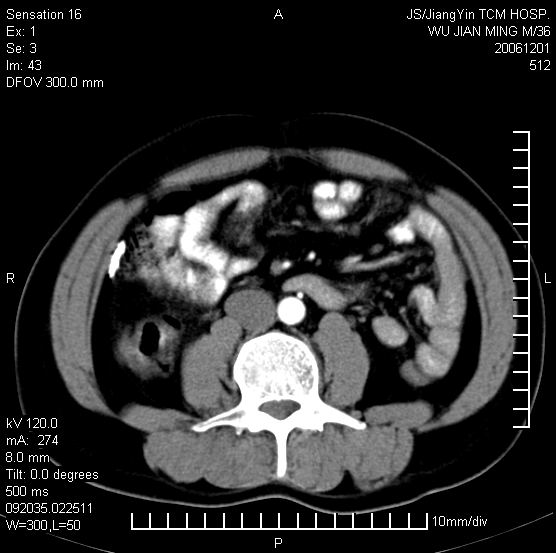

以下是引用dyqct在2006-12-1 21:17:00的发言:[br]左心缘旁及后肋膈窦区见巨大椭圆形混杂密度肿块,周围见大小不等斑片状钙化,内部无强化,周围包膜轻度强化,心脏明显受压变形,即明显占位效应,肿块广基与心包、膈相连。肝、脾内、肝门见多数小结节状钙化影。[br]考虑:1、左心缘旁及后肋膈窦区慢性包裹性胸膜炎(结核性);[br] 2、肝、脾及肝门淋巴结核已钙化。[br]

以下是引用zyx168在2006-12-2 10:10:00的发言:[br][br]肝脾肺内多发钙化灶